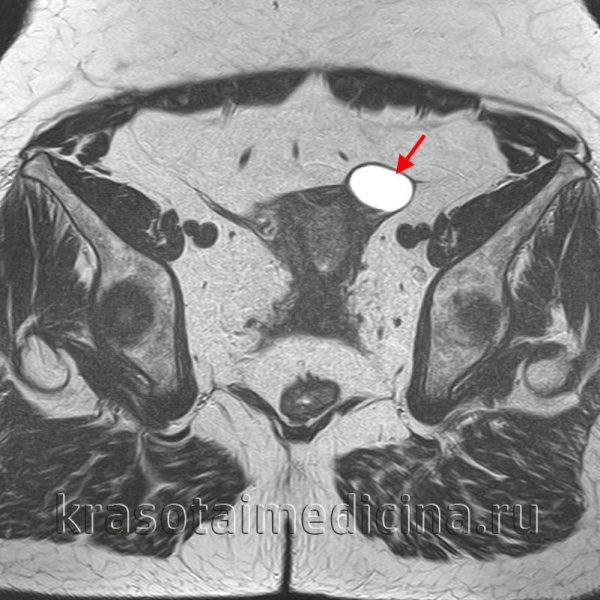

(Слева) УЗИ органов малого таза: типичная картина анэхогеной функциональной кисты с окружающей паренхимой яичника (отмечена калиперами).

(Справа) Функциональные кисты яичника могут увеличиваться, тогда окружающая паренхима яичника сжимается до тонкого ободка. Когда имеются такие проявления, как тазовая боль, необходимо использовать импульсную допплерографию для оценки форм колебаний артериального и венозного кровотоков.